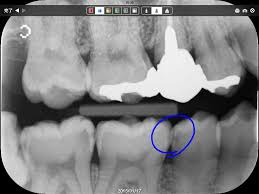

NHKの「ためしてガッテン」で「大人の悪性の虫歯」が紹介されました。街中で歯に自信がある人の8人中6人に虫歯が見つかりました。みんな自覚症状がないのでびっくりしていました。子供の頃は、歯が柔らかく歯の表面が溶けて穴があくので自分で分かりますが、大人の歯の表面は硬いので表面の穴は小さく中で広がっていきます。また、ゆっくり進行していくので自覚症状がほとんどありません。これが「大人の悪性の虫歯」です。歯科医院では疑いがあれば、レントゲンをとり診断します。虫歯が進行すると神経に炎症が起こり痛みが出ます。(これを歯髄炎といいます)。歯髄炎を起こすと神経をとる治療が必要になります。こうなると精神的、肉体的苦痛と時間とお金がかります。番組では半年に一度の検診を推奨しています。検診を受けて虫歯が進行しない生活を送ることが賢い生活です。今まで神経をとったり、歯を失ったことのある人は、特に予防検診をオススメします。